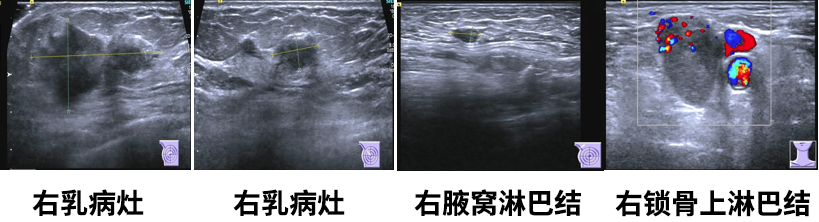

乳腺彩超

1.右乳肿物(约5.0*2.4*4.7cm),乳腺癌可能,BI-RADS5;

2.左乳切除术后,左胸壁未见明显异常;

3.右腋下(1.0*0.5cm)及右侧锁骨上淋巴结(2.6*1.8cm),转移可能。

右腋下淋巴结穿刺

见癌巢浸润,乳腺浸润性小叶癌转移可能性大。IHC:ER约95%中等-强(+)、TRPS1(+)、GATA-3(+)、CK5/6(-)、E-cadherin(-)、CgA(-)、Syn(-)。

右锁骨上淋巴结细针穿刺

见癌细胞。IHC:CK5/6(+)、P40(+)、TRPS1弱(+)、GATA-3个别弱(+)、E-cadherin膜(+)、P120膜(+)、ER(-)、PR(-)、HER-2(-)、CDX2(-),结合细胞形态和对比既往病理,考虑为鳞状细胞癌或伴有鳞状分化的癌可能性大。